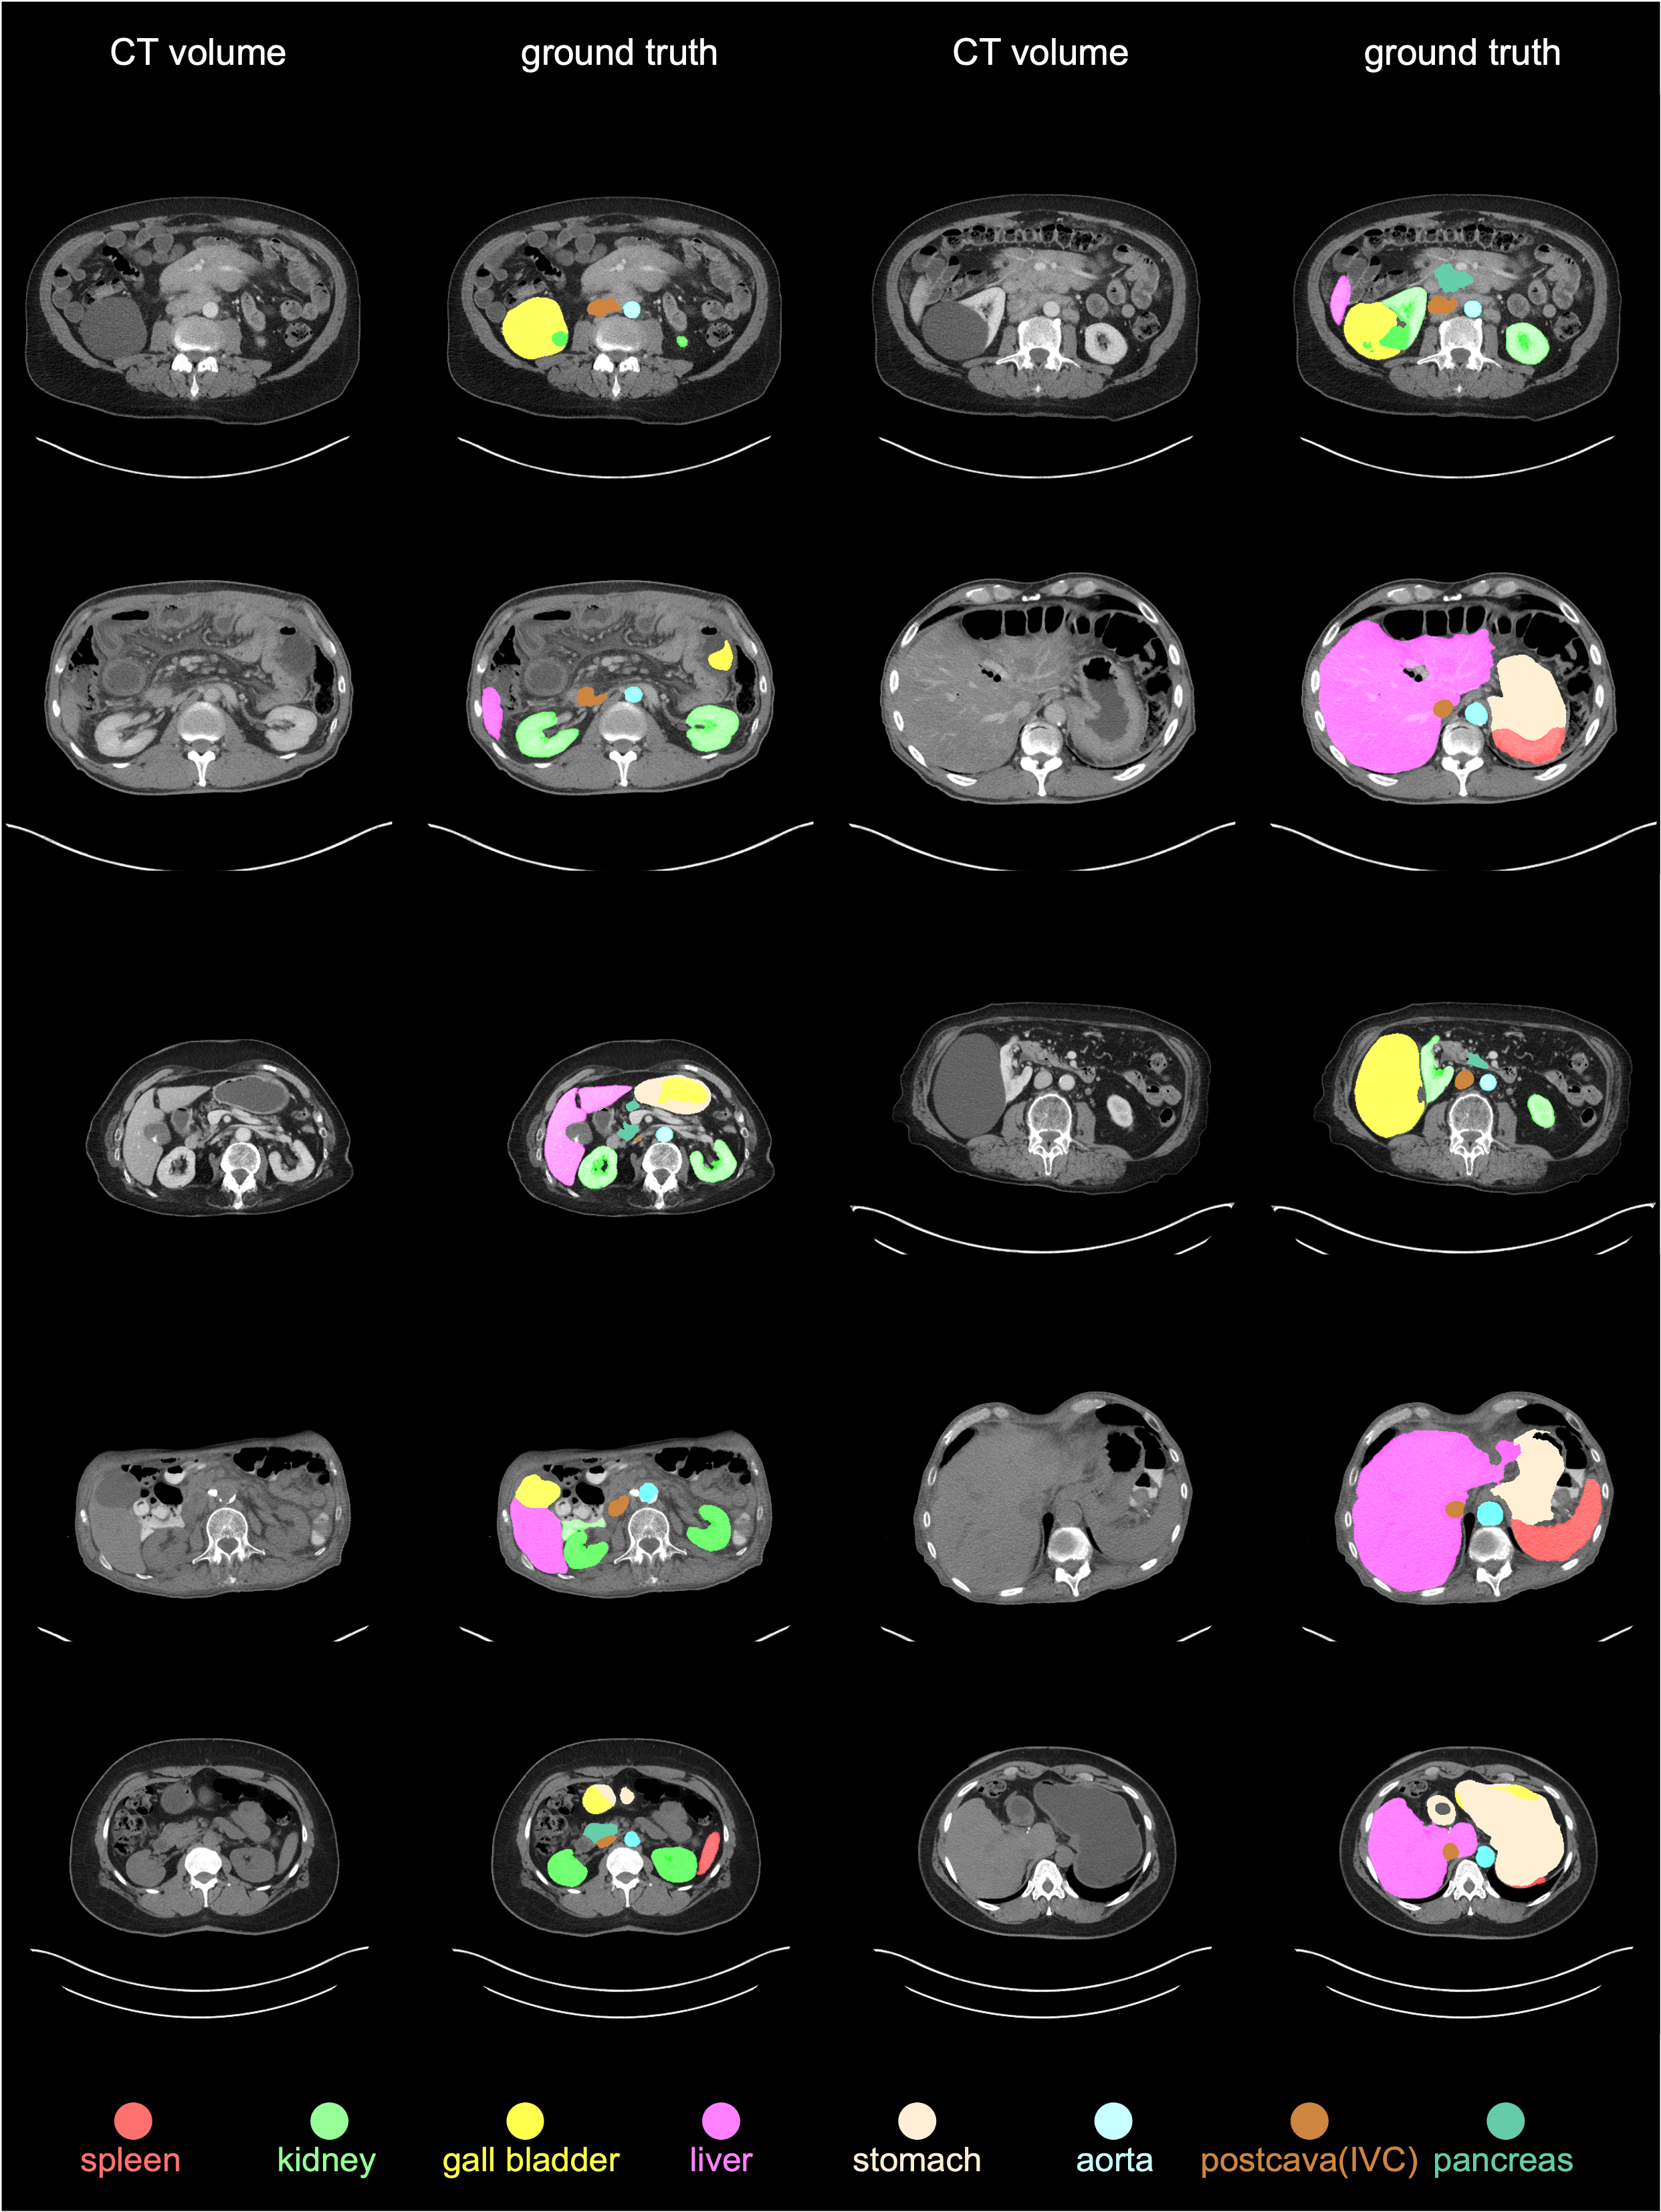

We used one training dataset and two test datasets to perform a comprehensive out-of-distribution benchmark. The training and test datasets were collected from many hospitals worldwide. Figure 1 shows the demographics of the two test datasets, JHH and TotalSegmentator; Appendix Figures 34 provide examples of CT scans and per-voxel annotations for various demographic groups across all datasets. The JHH dataset is proprietary and used for third-party evaluation; participants do not have access to the CT scans or their annotations. TotalSegmentator is a publicly available dataset; we did not inform the inventors beforehand of its use in our evaluation and confirmed that their AI algorithms had not been trained on this dataset. We included this public dataset to enable future participants to easily compare their algorithms with our benchmark.

AbdomenAtlas 1.0N𝑁Nitalic_N=5,195; publicly available for training purposes—is the largest multi-organ fully-annotated CT dataset to date, encompassing 76 hospitals in 8 countries [qu2023annotating]. It leveraged a human-in-the-loop active learning strategy to empower radiologists to feasibly annotate 5,195 CT scans from 16 public datasets (listed in Appendix Table 4) and is fully annotated for 9 anatomical structures, i.e., spleen, liver, L&R kidneys, stomach, gallbladder, pancreas, aorta, and postcava. AbdomenAtlas 1.0, under CC BY-NC 4.0 License, is derived from publicly available datasets, so detailed metadata information is unfortunately not available.